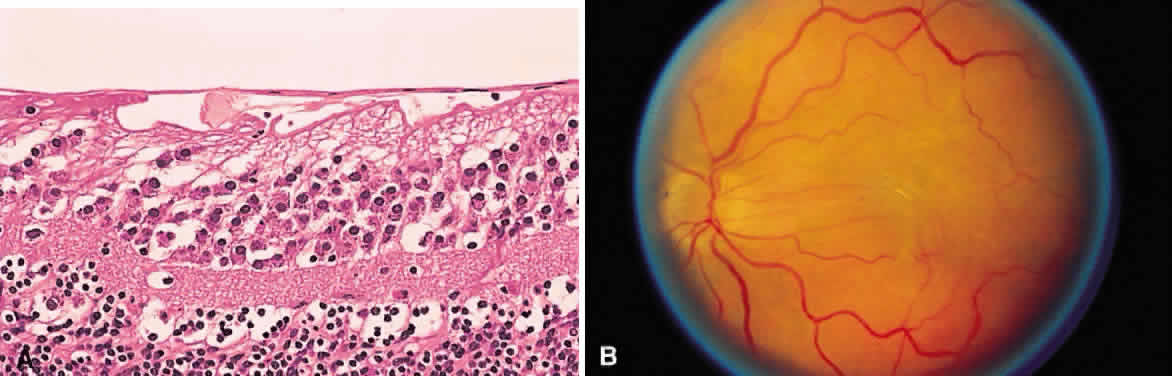

Fig. 17. A. A histologic section stained with H & E demonstrating vascularized

membranes on the disc and retina. Tractional retinal detachment is present. Notice

the subretinal fluid (amorphous eosinophilic material). B. Fundus photograph of fibrous tissue emanating from the disc in patient

with proliferative diabetic retinopathy. The disc is pale; the macula

is edematous with exudate. Pigmented laser spots are visible temporally. Fig. 17. A. A histologic section stained with H & E demonstrating vascularized

membranes on the disc and retina. Tractional retinal detachment is present. Notice

the subretinal fluid (amorphous eosinophilic material). B. Fundus photograph of fibrous tissue emanating from the disc in patient

with proliferative diabetic retinopathy. The disc is pale; the macula

is edematous with exudate. Pigmented laser spots are visible temporally.